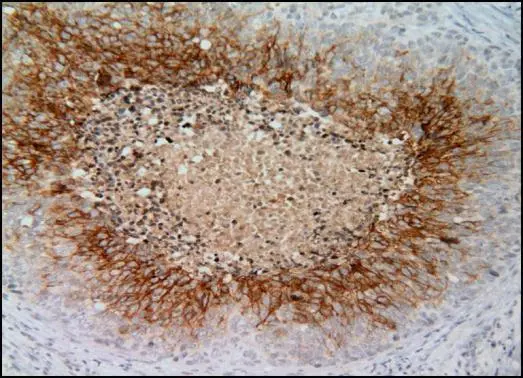

Anti-Carbonic Anhydrase IX antibody [GT12] used in IHC (Paraffin sections) (IHC-P). GTX70020

GTX70020 IHC-P Image

Immunohistochemical analysis of paraffin-embedded cervical CA tissue sections using anti-CAIX antibody [GT12] (GTX70020) at a dilution of 1:1000. The hypoxic regions of the tumor show positive CAIX staining.